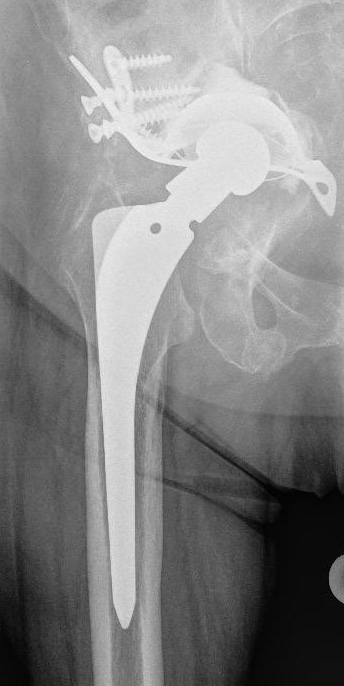

Materialien für den Prothesenwechsel

Der noch vorhandene Knochen muss bei einer Revision häufig mit Knochenersatzstoffen, Knochentransplantaten oder metallischem Knochenersatz verstärkt werden, um einen sicheren Halt der Wechselprothese zu gewährleisten. Mit Spezialimplantaten wie z. B. Abstützschalen an der Gelenkpfanne können wir auch in geschwächtem Knochen ein stabiles Implantat verankern. Oft eingesetzte Materialien für den Prothesenwechsel sind z. B.:

- Verstärkung der Hüftpfanne durch Sockel und Verschraubung

- Abstützschalen an der Hüftpfanne